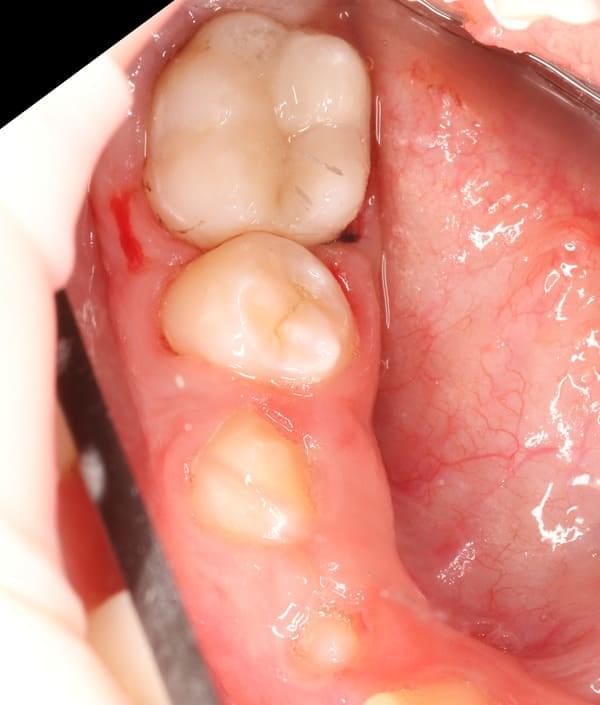

Робота з несформованими постійними зубами — найскладніша маніпуляція в дитячій стоматології. Ці зуби мають особливу будову, що ускладнює їх очищення та пломбування. У нашому Центрі Дитячої Стоматології в Києві ми володіємо передовими методиками, які дозволяють врятувати навіть найскладніші зуби.

Пульпа (нерв) постійного зуба має величезний потенціал до відновлення. Якщо це можливо, ми зберігаємо її, адже саме вона відповідає за ріст і повноцінне формування кореня. Зуб зі сформованим коренем значно міцніший і витриваліший.

Наші фахівці мають унікальний досвід у діагностиці та лікуванні несформованих постійних зубів. Вони точно знають, коли пульпу ще можна зберегти, а коли її необхідно видалити.